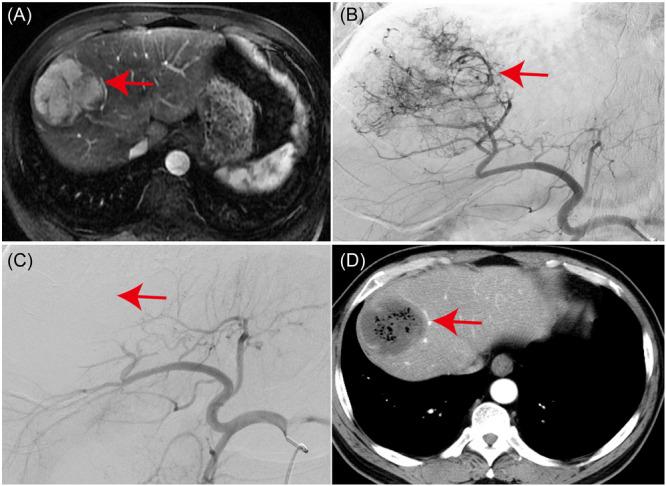

经动脉微球化疗栓塞术(mTACE)对肝癌髓系来源抑制细胞亚型的影响:临床相关性和治疗意义。

Impact of Microparticle Transarterial Chemoembolization (mTACE) on myeloid-derived suppressor cell subtypes in hepatocellular carcinoma: Clinical correlations and therapeutic implications.

This study aims to elucidate the alterations in MDSC subtypes, specifically monocytic MDSCs (mMDSCs) and early-stage MDSCs (eMDSCs), post-mTACE and to investigate their clinical correlations in HCC patients. A cohort comprising 75 HCC patients, 16 liver cirrhosis patients, and 20 healthy controls (HC) was studied. Peripheral blood samples were collected and analyzed for MDSC subtypes. The study also explored the associations between MDSC frequencies and various clinical parameters in HCC patients. The frequency of mMDSCs was significantly elevated in the HCC group compared to liver cirrhosis and HC. Importantly, mMDSC levels were strongly correlated with aggressive clinical features of HCC, including tumor size, vascular invasion, and distant metastasis. Post-mTACE, a marked reduction in mMDSC frequencies was observed, while eMDSC levels remained stable.

本研究旨在阐明 mTACE 后 HCC 患者 MDSC 亚型(单核细胞来源 MDSC[mMDSC]和早期 MDSC[eMDSC])的变化,并研究其与临床的相关性。研究纳入了 75 例 HCC 患者、16 例肝硬化患者和 20 例健康对照者(HC)。采集外周血样本来分析 MDSC 亚型。研究还探讨了 HCC 患者 MDSC 频率与各种临床参数之间的相关性。与肝硬化和 HC 相比,HCC 组的 mMDSC 频率明显升高。重要的是,mMDSC 水平与 HCC 的侵袭性临床特征,包括肿瘤大小、血管侵犯和远处转移密切相关。mTACE 后,mMDSC 频率明显降低,而 eMDSC 水平保持稳定。